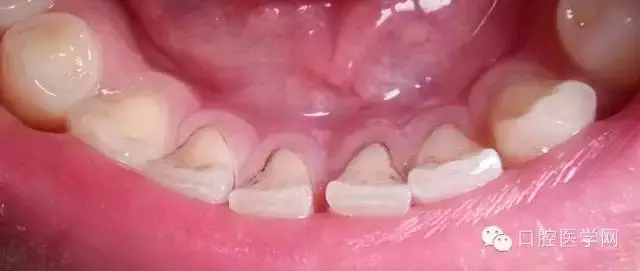

有人會發(fā)現(xiàn),自己的牙齒表面突然出現(xiàn)一點(diǎn)黑點(diǎn),但是也不覺得疼,是什么原因?qū)е卵例X變黑?如果牙齒出現(xiàn)黑點(diǎn)且不痛有兩種可能性。

一旦確認(rèn)牙齒上的小黑點(diǎn)是齲齒就應(yīng)該盡早修補(bǔ),以阻止病變的發(fā)展。如果任由其繼續(xù)發(fā)展就會變成明顯的齲洞,這時患者會對冷熱酸甜等食物刺激敏感;當(dāng)損傷進(jìn)一步到達(dá)牙髓(即老百姓說的“牙神經(jīng)”),就會疼痛難忍,嚴(yán)重影響日常生活。臨床上見到很多人都會等到牙痛得受不了,才到醫(yī)院就診。這時通常不能靠單純補(bǔ)牙來解決問題,可能還要做根管治療甚至拔除患牙、進(jìn)行假牙修復(fù),費(fèi)時費(fèi)力又費(fèi)錢,人還遭罪,可謂“小洞不補(bǔ),大洞吃苦”。